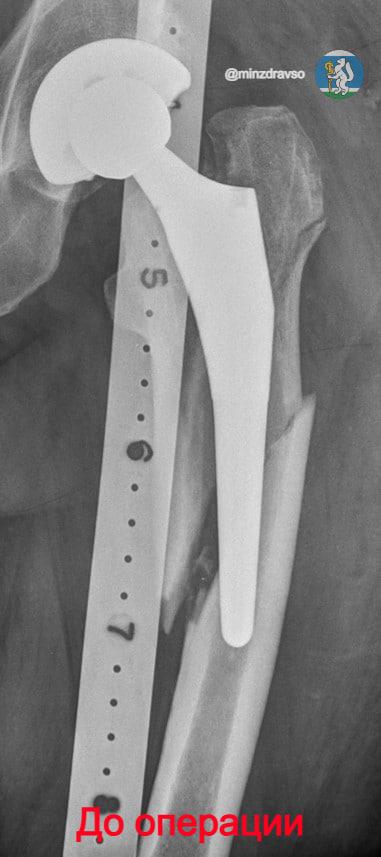

«Суть метода — в ювелирной точности и индивидуальном подходе. Перед операцией врачи тщательно планируют каждый шаг по рентгеновским снимкам, затем для пациента изготавливают специальные стержни, которые надёжно фиксируют протез. Вмешательство проводится малоинвазивно: стержень вводится с обратной стороны, что позволяет пациенту практически сразу опираться на прооперированную ногу. Для восстановления анатомии созданы уникальные устройства, а для безопасного удаления старого цемента — специальный инструмент, который не повреждает кость», — сообщили в минздраве региона.

Там также отметили, что раньше лечение переломов вокруг эндопротезов бедра было долгим и травматичным: большие разрезы, значительная кровопотеря, высокий риск осложнений. Даже после успешной операции кость могла не срастись, а повторное вмешательство требовалось почти каждому четвёртому пациенту.